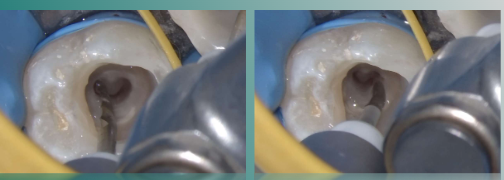

局部黏膜碘伏消毒,4%阿替卡因局部浸润麻醉+牙周膜麻醉下,去尽腐质,远中制作假壁,开髓,揭顶,暴露髓腔。

3%次氯酸钠大量冲洗,清理冠髓,暴露根管口,可见根管呈连续C形。

欧罗德卡U系列开口锉1508,去除根管口牙本质领,打开根管中上段,建立直线通路。

10#手用不锈钢器械尖端预弯,测量各根管工作长度,并建立光滑通道。

3%次氨酸钠大量冲洗根管

欧罗德卡U系列通道锉1203对各根管进行疏通,确保通道顺滑,以便后续序列锉进入。